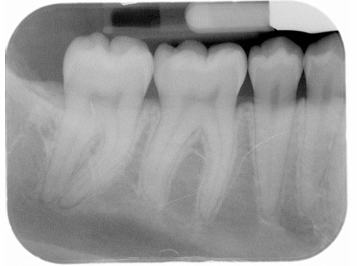

What is the problem with this Overlapped contacts X-ray?

Central ray not directed through the interproximal spaces

How would you resolve this Overlapped contacts X-ray?

Direct the x-ray beam through the contacts